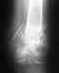

1 апреля 2006 года в ДТП получены много оскольчатые переломы голени на одной ноге и бедра на другой. Установлены аппараты Илизарова.На голени убирали дистракцию, а на бедре транформацию кости (меняли угол кайками в течение месяца). Сейчас сказали, что можно давать нагрузку на обе ноги, но мешают сильные боли. Как правильно организовать процесс стояния и обучения ходьбе на обеих смоманных ногах? Нужны ли занития ЛФК? Какие?

Вопрос о нагрузке уместнее обсудить с Вашим врачом - возможно, на месте виднее, с чам связаны боли. Занятия нужны, они направлены на восстановление амплитуды движений в голеностопном (там, где перелом голени) и коленнном суставах. Вообще, на сегодня практикуется смена внешнего фиксатора на внутренний (гвоздь с блокированием). Что позволяет избежать прошивания мышц спицами, и остальных неудобств аппаратов. можно сгибать, нагружать конечности.